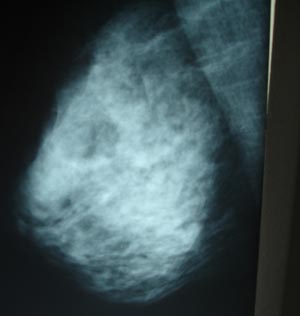

Carcinoma of breast. Mammogram showing irregular soft tissue mass. Microcalcifications are present but difficult to see in reproduction.